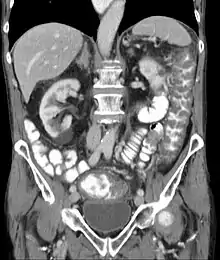

Pseudomembranous colitis on computed tomography

Prior to the advent of tests to detect C. difficile toxins, the diagnosis most often was made by colonoscopy or sigmoidoscopy. The appearance of "pseudomembranes" on the mucosa of the colon or rectum is highly suggestive, but not diagnostic of the condition.[43] The pseudomembranes are composed of an exudate made of inflammatory debris, white blood cells. Although colonoscopy and sigmoidoscopy are still employed, now stool testing for the presence of C. difficile toxins is frequently the first-line diagnostic approach. Usually, only two toxins are tested for—toxin A and toxin B—but the organism produces several others. This test is not 100% accurate, with a considerable false-negative rate even with repeat testing.[44]